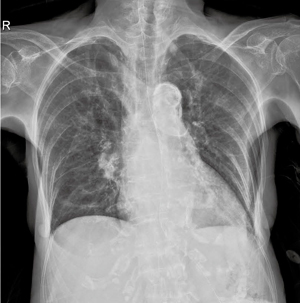

■Mobilett Miraによる臨床画像

検査目的:右下肺肺炎フォローアップ |

Mobilett Miraは,最大35kW,450mA,最短1msの大出力のX線管の搭載により短時間の照射を可能にし,一般撮影装置と同等の高画質を実現する。長尾科長は,高出力X線管のメリットについて,「FDになったことで,画素数が増えダイナミックレンジやSNRが向上したのと同時に,450mAまで管電流を上げられることで,息止めが困難なケースや意識がない患者さんの撮影の際に威力を発揮します。大電流,短時間撮影ができることは大きなポイントになりました」と述べている。

長尾科長はグリッドなしの画質について,「胸部の画像はもちろんですが,より散乱線の多い腹部の撮影でも予想以上の画像が得られました。グリッド装着時の干渉による再撮影の可能性と,ポータブルの病棟撮影に求められる画質とを勘案し,病棟では基本的にグリッドなしで撮影を行うようになりました」と説明する。